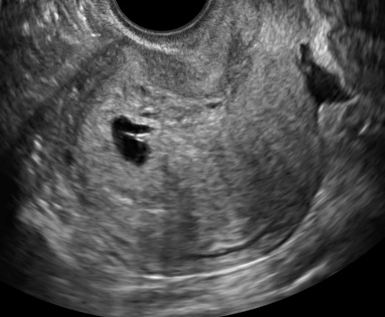

8 稽留流産の診断 日本産婦人科医会

8 稽留流産の診断 日本産婦人科医会

8 稽留流産の診断 日本産婦人科医会